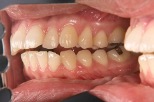

下の前歯がほとんど見えない位に上の前歯がかぶさっている状態のことです。正常な状態では奥歯で噛んだ時に、下の前歯が上の前歯の裏側に軽く触れていますが、過蓋咬合では下の前歯の切端は、歯ではなく上の前歯の内側の歯茎を噛んでいることもあります。

歯の大きさや傾斜角にもよりますが、上の前歯と舌の前歯の重なり(オーバーバイト)は2~4ミリが正常値ですので、それより大きいと過蓋咬合に分類されます(図1,2、3、4、5)。

図1過蓋咬合(前から)

図2過蓋咬合(横から)